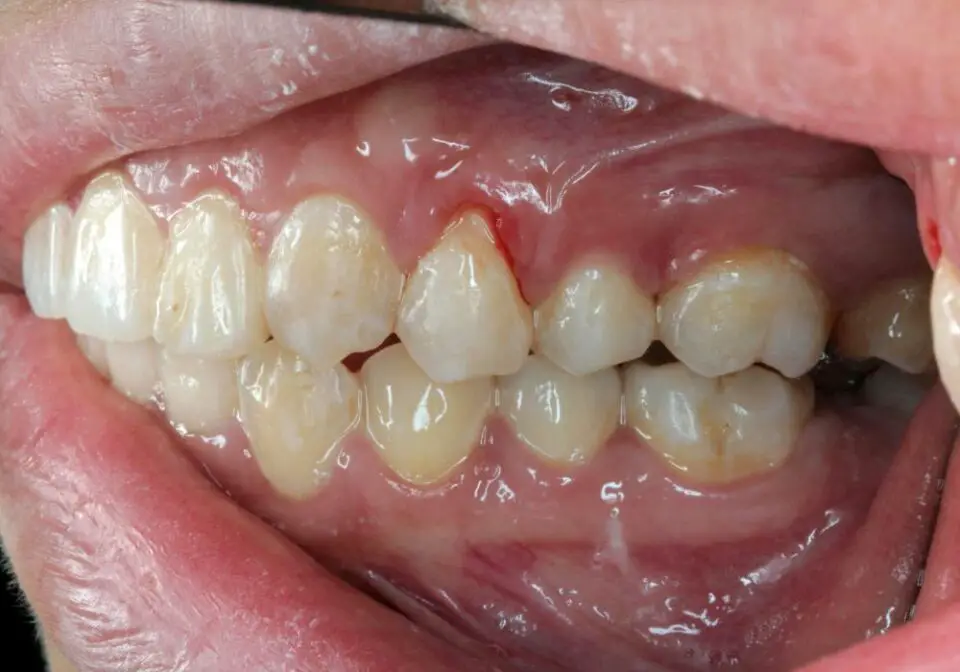

Gums That Have Pulled Away From Your Teeth . You may also hear the terms gum recession or gingival recession. If you have receding gums, you’ll be able. Receding gums are gums that pull away from the underlying teeth. Receding gums refer to when gums wear away or become pushed back, exposing the roots of the teeth. Healthcare professionals refer to it as a gingival recession, a. Receding gums occurs when your gums pull back from the tooth surface, exposing the root surfaces of your teeth. Gum recession is the process in which the margin of the gum tissue that surrounds the teeth wears away, or pulls back, exposing. Receding gums is when the gums pull back from the teeth, exposing each tooth and its roots further. In doing so, it exposes more of the roots of the tooth it surrounds. Receding gums become a health concern, leaving the teeth at risk of. Receding gums, or gingival recession, is an oral condition in which your gum tissue wears away or retracts. Treatment can include medications, surgical. A change in the way your teeth fit together when you bite. Gums that pull away from your teeth, making your teeth look longer than usual, called receding gums.